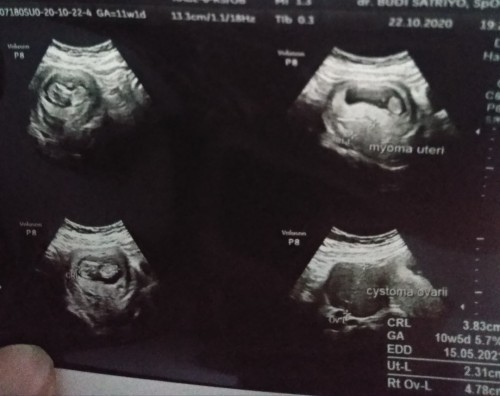

Hamil ada kista dan miom

Assalamualaikum bunda.. Saya hmil 11 minggu,stelah di usg alhamdulilah janinya sehat tpi ada kista & miom bun..pikiran udh kemana2,tpi dokter'y bilang "udah gk ppa,jngan dipikirin". Ada yg punya pngalaman kya sya gk bun,tlong ksih sran sy harus gimana😭 #bantusharing #seriusnanya #firstbaby